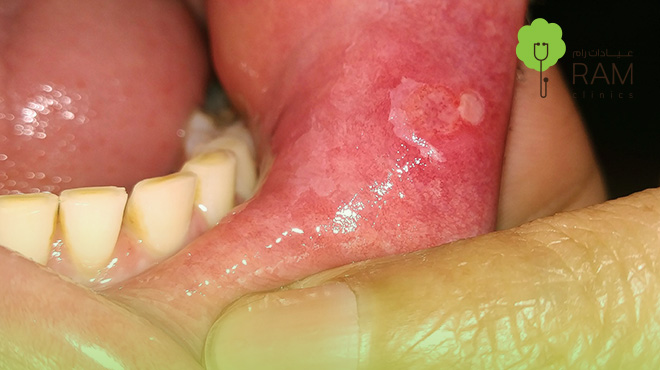

شكل سرطان اللثة بالصور

شكل سرطان اللثة بالصور يظهر اختلافات واضحة عن الشكل الطبيعي للثة الصحية، حيث يبدو النسيج المصاب أكثر خشونة، وتظهر عليه بقع أو تقرحات بارزة، وعلى الرغم من أن التشخيص لا يعتمد على الصور فقط، فإن ملاحظتها تساعد في معرفة العلامات التي تستدعي القلق.

أبرز السمات في شكل سرطان اللثة بالصور

• بقع حمراء داكنة أو بيضاء باهتة تظهر في شكل سرطان اللثة بالصور.

• انتفاخات أو تكتلات صلبة تحت اللثة أو في محيط الأسنان، تظهر في شكل سرطان اللثة بالصور.

• تآكل في أنسجة اللثة يجعل الأسنان تبدو أطول من المعتاد، في شكل سرطان اللثة بالصور.

• نزيف متكرر من أماكن محددة حتى مع تنظيف بسيط للأسنان.

• تغير في لون اللثة لتصبح أغمق أو باهتة في شكل سرطان اللثة بالصور مقارنة بالمناطق السليمة.

• تقرحات مفتوحة يصعب التئامها وتصدر رائحة فم كريهة مستمرة.

ورغم أن شكل سرطان اللثة بالصور قد يعطي فكرة عامة عن شكل سرطان اللثة، إلا أن التشخيص الدقيق لا يمكن أن يتم إلا من خلال فحص الطبيب المختص باستخدام أدوات وتقنيات متقدمة مثل الفحص البصري أو الخزعة النسيجية.